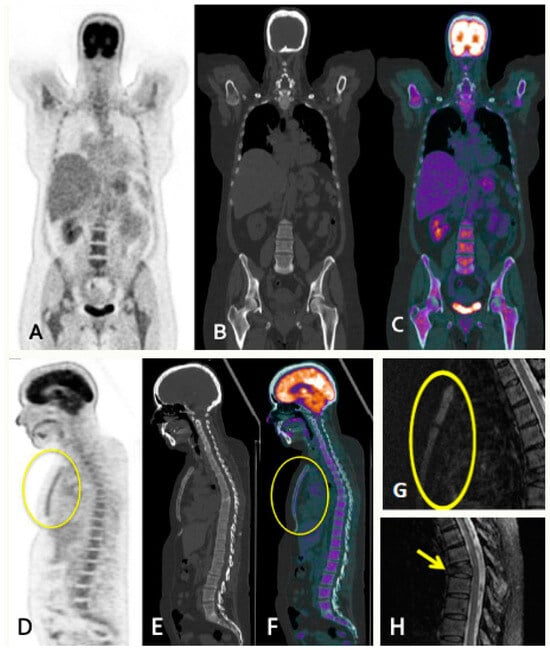

- Diffuse pattern: Diffuse disease can be suspected from a diffuse decreased signal on T1WI (either iso- or hypointense to intervertebral discs and muscle) and a diffuse increased signal throughout the marrow on T2FSWI, STIR, or high b-value DWI. Marrow ADC values above 600–700 μm2/s in a nontreated and newly diagnosed patient with MM could be used to increase confidence for the diagnosis of diffuse marrow involvement [33] (Figure 7). Due to potential false-positive findings, diffuse disease in imaging must be supported by bone marrow trephine biopsy [26].

5.1. PET/CT

5.1.5. FDG-PET/CT vs. WBMRI